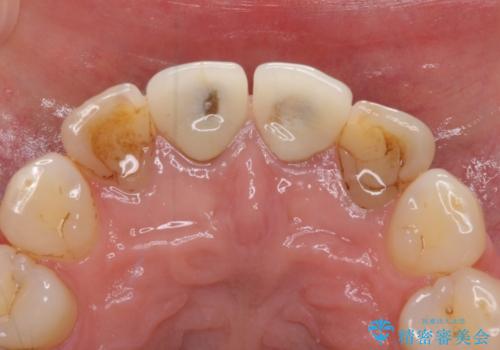

- 前歯のクラウンの変色や歯の変色を気にして来院された患者様です。

グラスファイバーを用いた土台により歯質を強化した上で、オールセラミッククラウンにて補綴することとしました。